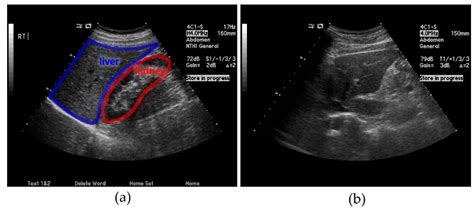

Interpreting the results of a liver ultrasound involves assessing the images for any abnormalities. A normal liver ultrasound will show:

• Size and Shape: The liver should be of normal size and shape, with smooth edges.

• Echogenicity: The liver tissue should have a uniform echogenicity, indicating a healthy structure.

• Blood Flow: Normal blood flow through the liver and its vessels.

• Absence of Abnormalities: No cysts, tumors, or other abnormalities should be present.